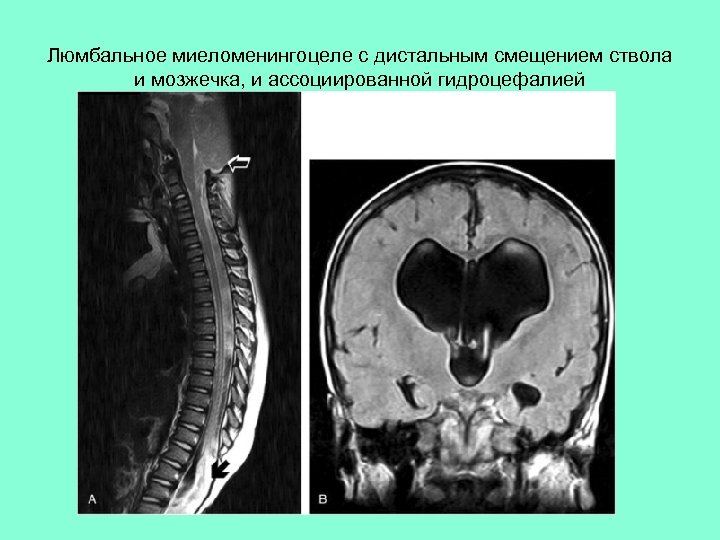

Люмбальное миеломенингоцеле с дистальным смещением ствола и мозжечка, и ассоциированной гидроцефалией